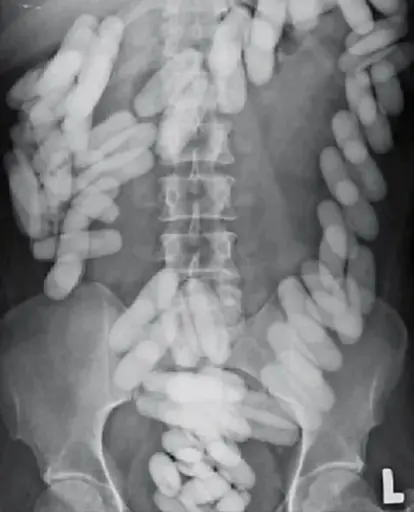

Wtf am I looking at?

Probably someone who’s had major bone reconstruction

do you know they’re stir bars? they look puffy and the magnet would be opaque…

Please tell me these are cocaine condoms and not actual stir bars like I thought when I first woke up and saw this

Sadly this is probably from a child who ate a bunch of magnets.

Lab stir bars are Teflon coated and look like candy. No idea where anyone could find that many stir bars.

Is it not cocain smuggling via eating pods?

Maybe you’re right, but the hips look very small and the objects very uniform.